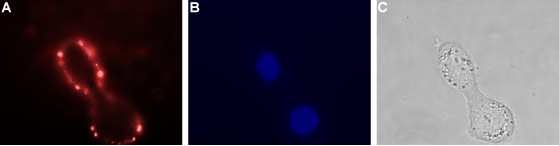

Expression of VPAC1 in human HT-29 cellsCell surface detection of VPAC1 in live intact human HT-29 colorectal adenocarcinoma cells. A. Extracellular staining of live cells with Anti-VPAC1 (VIPR1) (extracellular) Antibody (#AVR-001), (1:25), followed by goat anti-rabbit-AlexaFluor-594 secondary antibody (red). B. Cell nuclei were visualized using Hoechst 33342 (blue). C. Live view of the cells.

Expression of VPAC1 in human HT-29 cellsCell surface detection of VPAC1 in live intact human HT-29 colorectal adenocarcinoma cells. A. Extracellular staining of live cells with Anti-VPAC1 (VIPR1) (extracellular) Antibody (#AVR-001), (1:25), followed by goat anti-rabbit-AlexaFluor-594 secondary antibody (red). B. Cell nuclei were visualized using Hoechst 33342 (blue). C. Live view of the cells.